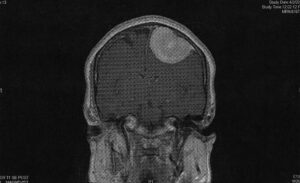

With that, Dr. Modi picked the two papers from the bed and handed them to me. They were two black-and-white MRI scanned images. From the side and back views, the bones of my skull glowed white against the black film. I easily located the dark areas of my eye socket and sinus cavity. Behind them sat the folds and wrinkles of my brain.

Amidst the brain matter, a light gray mass more than twice the size of my eye socket was adhered to my skull. Studying the second image—a posterior view of my skull—I realized  the tumor filled approximately a quarter of the area meant for my brain.

the tumor filled approximately a quarter of the area meant for my brain.